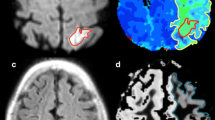

Inadequate blood supply relative to metabolic demand, a haemodynamic condition termed as misery perfusion, often occurs in conjunction with acute ischaemic stroke. Misery perfusion results in adaptive changes in cerebral physiology including increased cerebral blood volume (CBV) and oxygen extraction ratio (OER) to secure substrate supply for the brain. It has been suggested that the presence of misery perfusion may be an indication of reversible ischaemia, thus detection of this condition may have clinical impact in acute stroke imaging. The ability of single spin echo T2 to detect misery perfusion in the rat brain at 1.5 T owing to its sensitivity to blood oxygenation level dependent (BOLD) contrast was studied both theoretically and experimentally. Based on the known physiology of misery perfusion, tissue morphometry and blood relaxation data, T2 behaviour in misery perfusion was simulated. The interpretation of these computations was experimentally assessed by quantifying T2 in a rat model for cerebral misery perfusion. CBF was quantified with the H2 clearance method. A drop of CBF from 58 ± 8 to 17 ± 3 ml/100 g min in the parieto-frontal cortex caused shortening of T2. from 66.9 ± 0.4 to 64.6 ± 0.5 ms. Under these conditions, no change in diffusion MRI was detected. In contrast, the cortex with CBF of 42 ± 7 ml/100 g min showed no change in T2. Computer simulations accurately predicted these T2, responses. The present study shows that the acute drop of CBF by 70% causes a negative BOLD that is readily detectable by T2 MRI at 1.5 T. Thus BOLD may serve as an index of misery perfusion thus revealing viable tissue with increased OER.